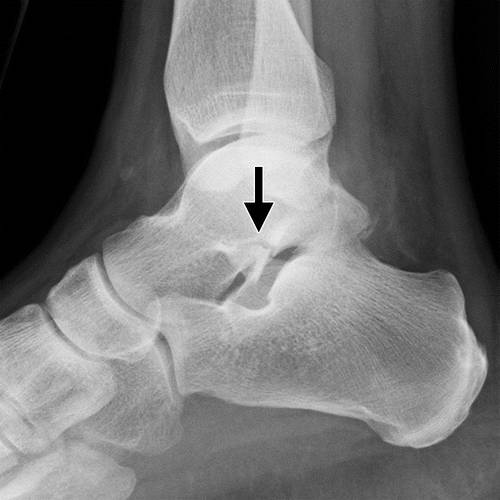

图11b外侧距骨软骨骨折。 (a)踝关节的AP射线照片显示外侧的距骨穹顶(箭头)的微妙的骨软骨骨折,被重叠的腓骨遮蔽。 (b)脚踝的斜位视图更好地显示骨折(箭头)。

图12a内侧踝关节骨软骨骨折。 AP(a)和斜位(b)踝骨的X线照片显示椎间融合器的移位骨软骨骨折(黑色箭头)。 还注意到倾斜的骨干腓骨骨折(箭头),syndesmotic加宽(双头箭头)和内侧清晰空间加宽(白色箭头b),符合syndesmotic和三角肌韧带复杂损伤的存在。